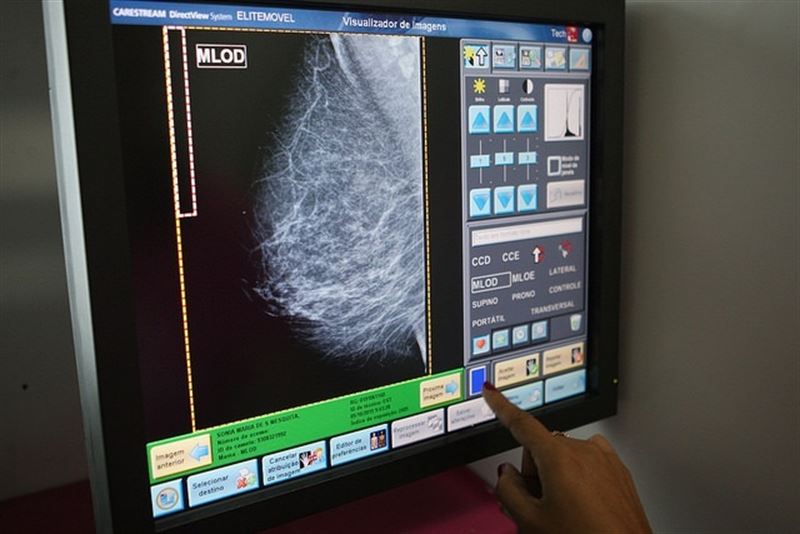

fotonoticia_20160104081438_800El uso del ultrasonido (US) en la detección de cáncer de mama ha demostrado ser comparable en su sensibilidad a la de la mamografía y se debe tener en cuenta para su análisis de la enfermedad, según un estudio publicado este lunes en ‘JNCI: Journal of the National Cancer Institute’.

El número de cánceres de mama está aumentando en todo el mundo, con más de 1,6 millones de nuevos casos de la enfermedad en 2010, lo que resulta en la muerte de más de 425.000 mujeres. Además, se esperan 2,1 millones de nuevos casos de cáncer de mama para el año 2030. Aunque la mamografía es un método eficaz en la detección de cáncer de mama en los países desarrollados, no está comúnmente disponible en los países menos desarrollados y se tienen que examinar métodos alternativos, como la ecografía.